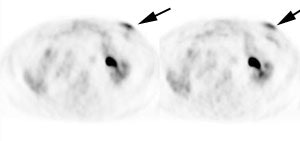

Genitourinary activity: The image below demonstrates activity within the collecting system of a transplanted kidney (black arrows). This should not be mistaken for an abnormality. |

|

|

|

Bladder cancer: Dilute urinary activity in this patient's bladder allowed accurate detection of their bladder cancer (white arrows on CT, black arrows on PET scan). In general, urinary excretion of FDG limits evaluation of urinary tract malignancies, however, hydration and diuresis can improve diagnostic accuracy. |

|

|